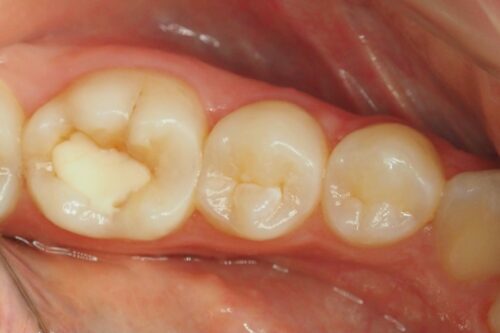

Ząb z nieszczelnym wypełnieniem na powierzchni zgryzowej i próchnicą

Opracowano ubytek próchnicowy oraz wykonano anatomiczną odbudowę materiałem kompozytowym